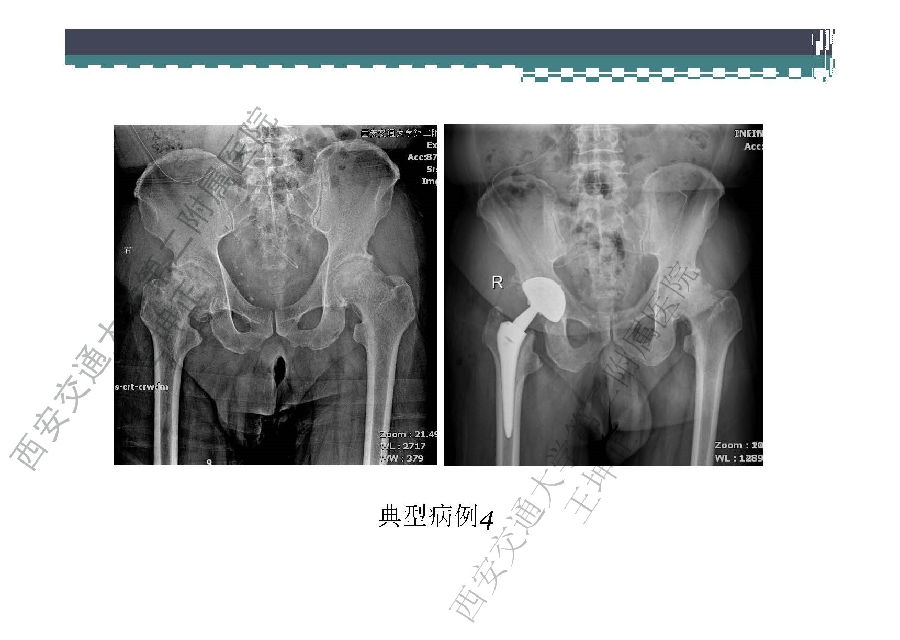

对于关节外科而言快速康复实际上是以病人加速舒适康复为目的,加强围术期的综合管理,包括疼痛和睡眠管理、血栓预防管理、感染预防管理、围术期血液管理,减少放置引流管、尿管、减少止血带应用,减少术后恶心呕吐,尽早进食,尽早康复等,逐步达到无血、无痛、无栓、无感、无肿、无管、无吐、无带等优良效果。为此,小编特邀王坤正教授等多位关节外科的专家参与撰写快速康复外科在关节外科的应用的主题文章,共话“人工关节置换快速康复”新理念,探讨建立符合我国特色的关节置换围手术期管理与快速康复体系,促进我国关节外科技术整体发展与提高。